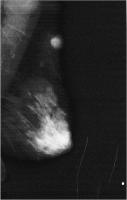

Fallbericht: Ein ungewöhnlicher Fall eines solitären Knotens in der Brust als Erstmanifestation eines anaplastischen Schilddrüsenkarzinoms